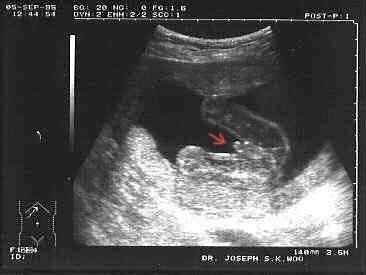

tuhle fotečku mám z videa ze 4D a je to pohled ze spodu na prdelku a nožičky...předem děkuji všem za snahu

já bych to přirovnala asi k tomuto obrázku,ale fakt se to blbě určuje

,Ahoj Milu, tak přesně takovou fotku jako jsi dala v dalším příspěvku mám já z UZ, když jsem před 3 lety čekala našeho kulíška, přesně zespoda jakoby seděl na průhledný židličce a narodil se nám kluk jako buk škoda, že je mám vlepené v jeho knížce a ne naskenované v compu hodila bych ji sem na těch dalších UZ obrázcích je tam jasnej pindík

[8997]

jj tak to vypadá,jak když sedí na průhledné stoličce...tak to je škoda,bych se ráda podívala a porovnala...no uvidíme co to bude

no když na to koukám a srovnám,tak jsem si jistá že to bude klučina